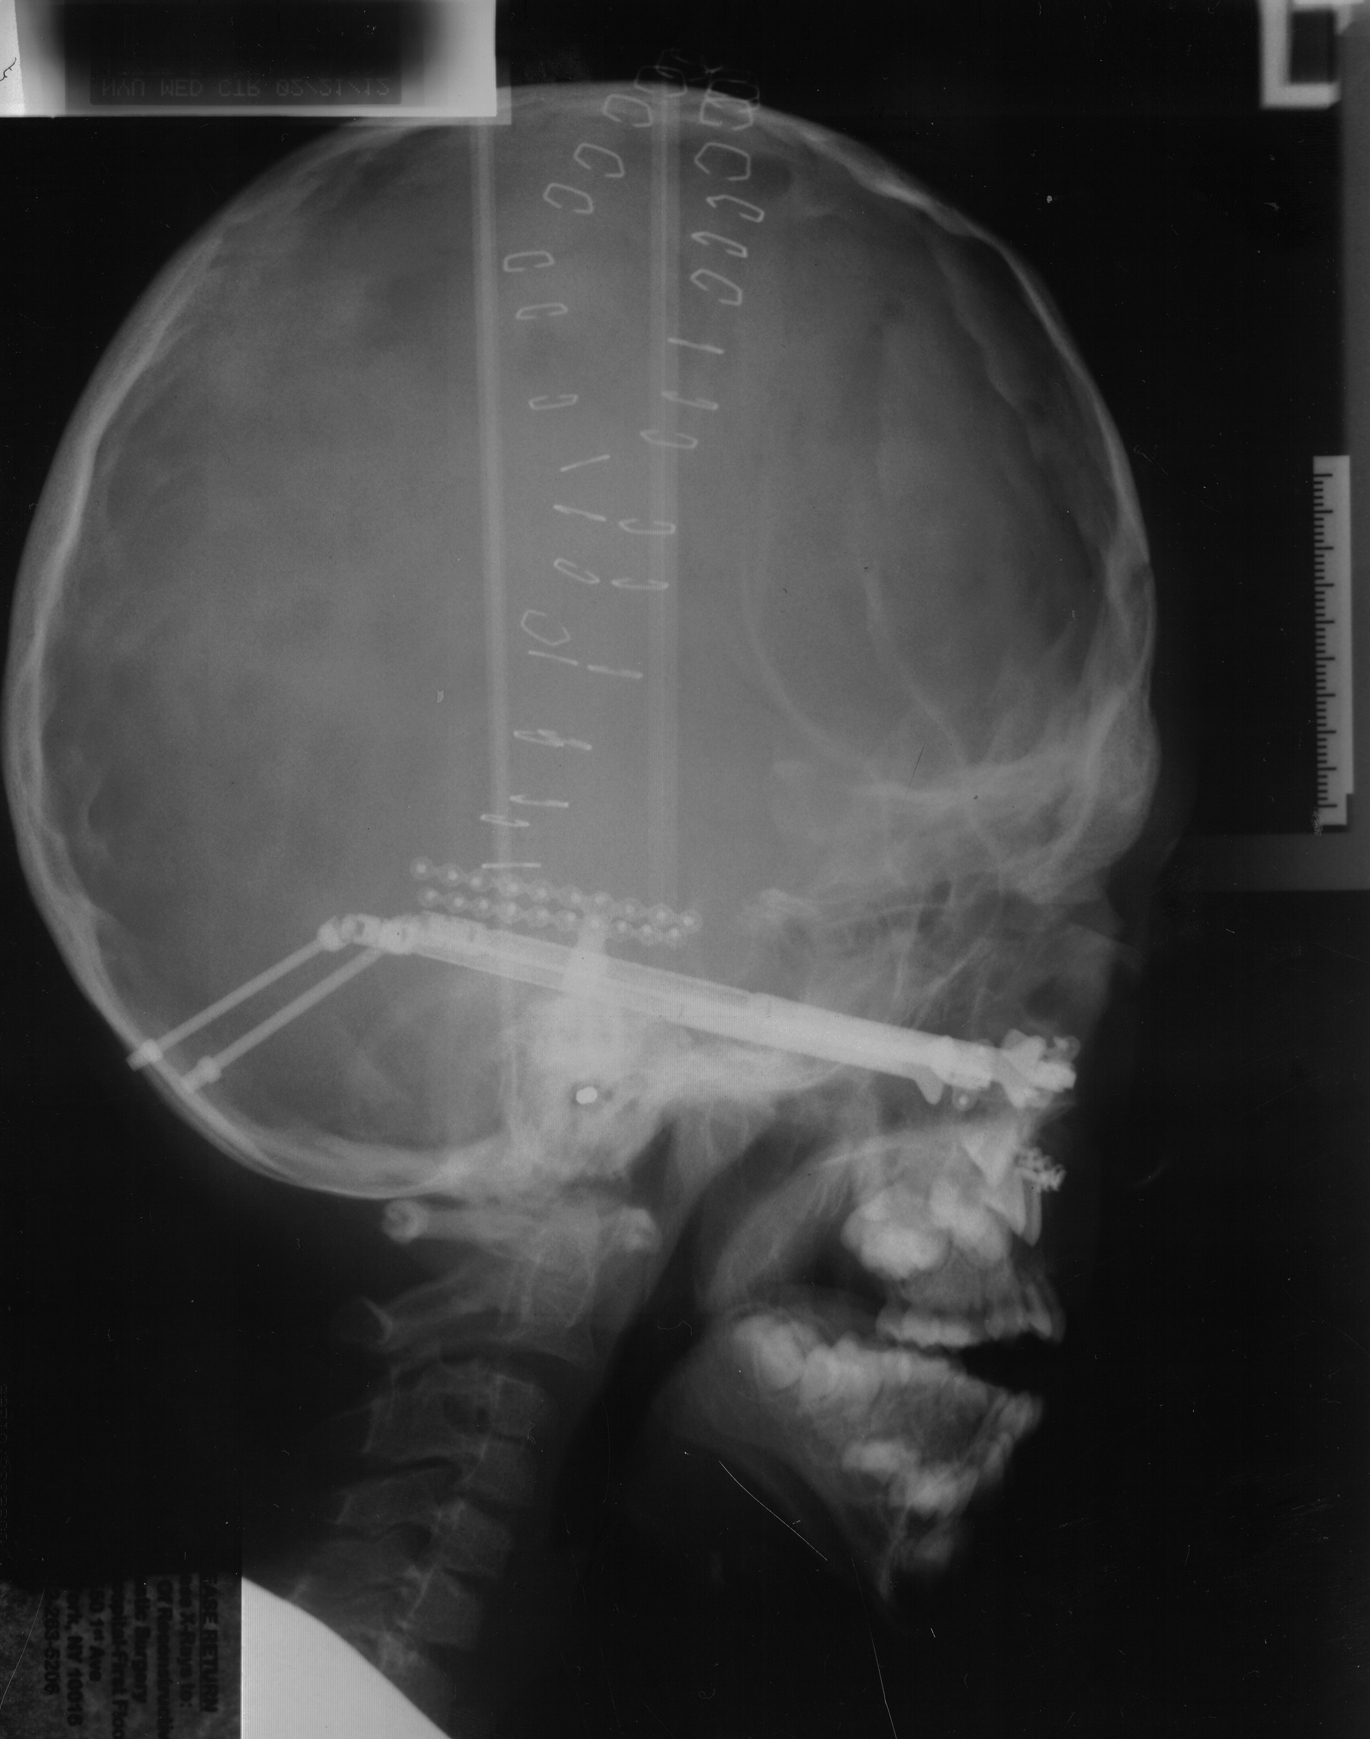

Cephalograms can be obtained preoperatively and subsequently repeated postoperatively to determine the degree of translation and rotation of the Le Fort III segment during device activation. On occasion, the patient’s age or behavioral factors may make reliable cephalograms impossible, whereas CT scans may be performed with anesthesia.

Internal Distractor Placement